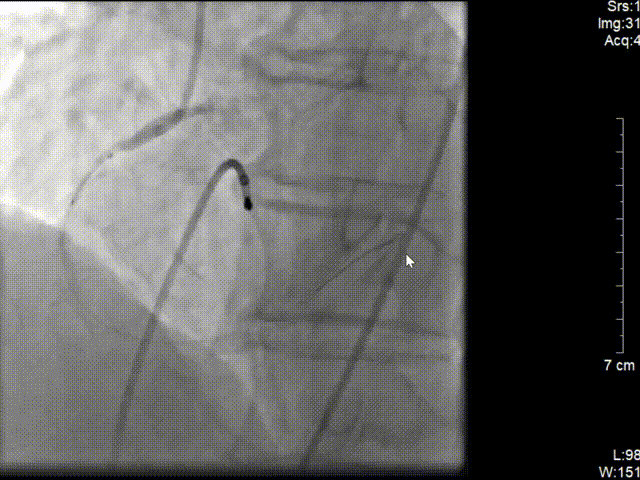

左图:6F JR4.0指引导管造影。

右图:右冠远段、近段各植入药物支架1枚。

再次予2.0*15预扩张球囊行病变处预扩张处理,右冠近中置入3.5*40mm药物支架1枚,继续予以3.5*15m后扩张球囊行支架内优化扩张。

复查造影可见右冠远段狭窄80%,并见血栓,予2.0*15预扩张球行右冠远段病变处预扩张,于右冠远段置入2.5*14mm 药物支架1枚,并予以3.0*12mm后扩张球囊行支架内扩张优化。再次造影示右冠狭窄消失,无夹层及残余狭窄,TIMI血流3级。